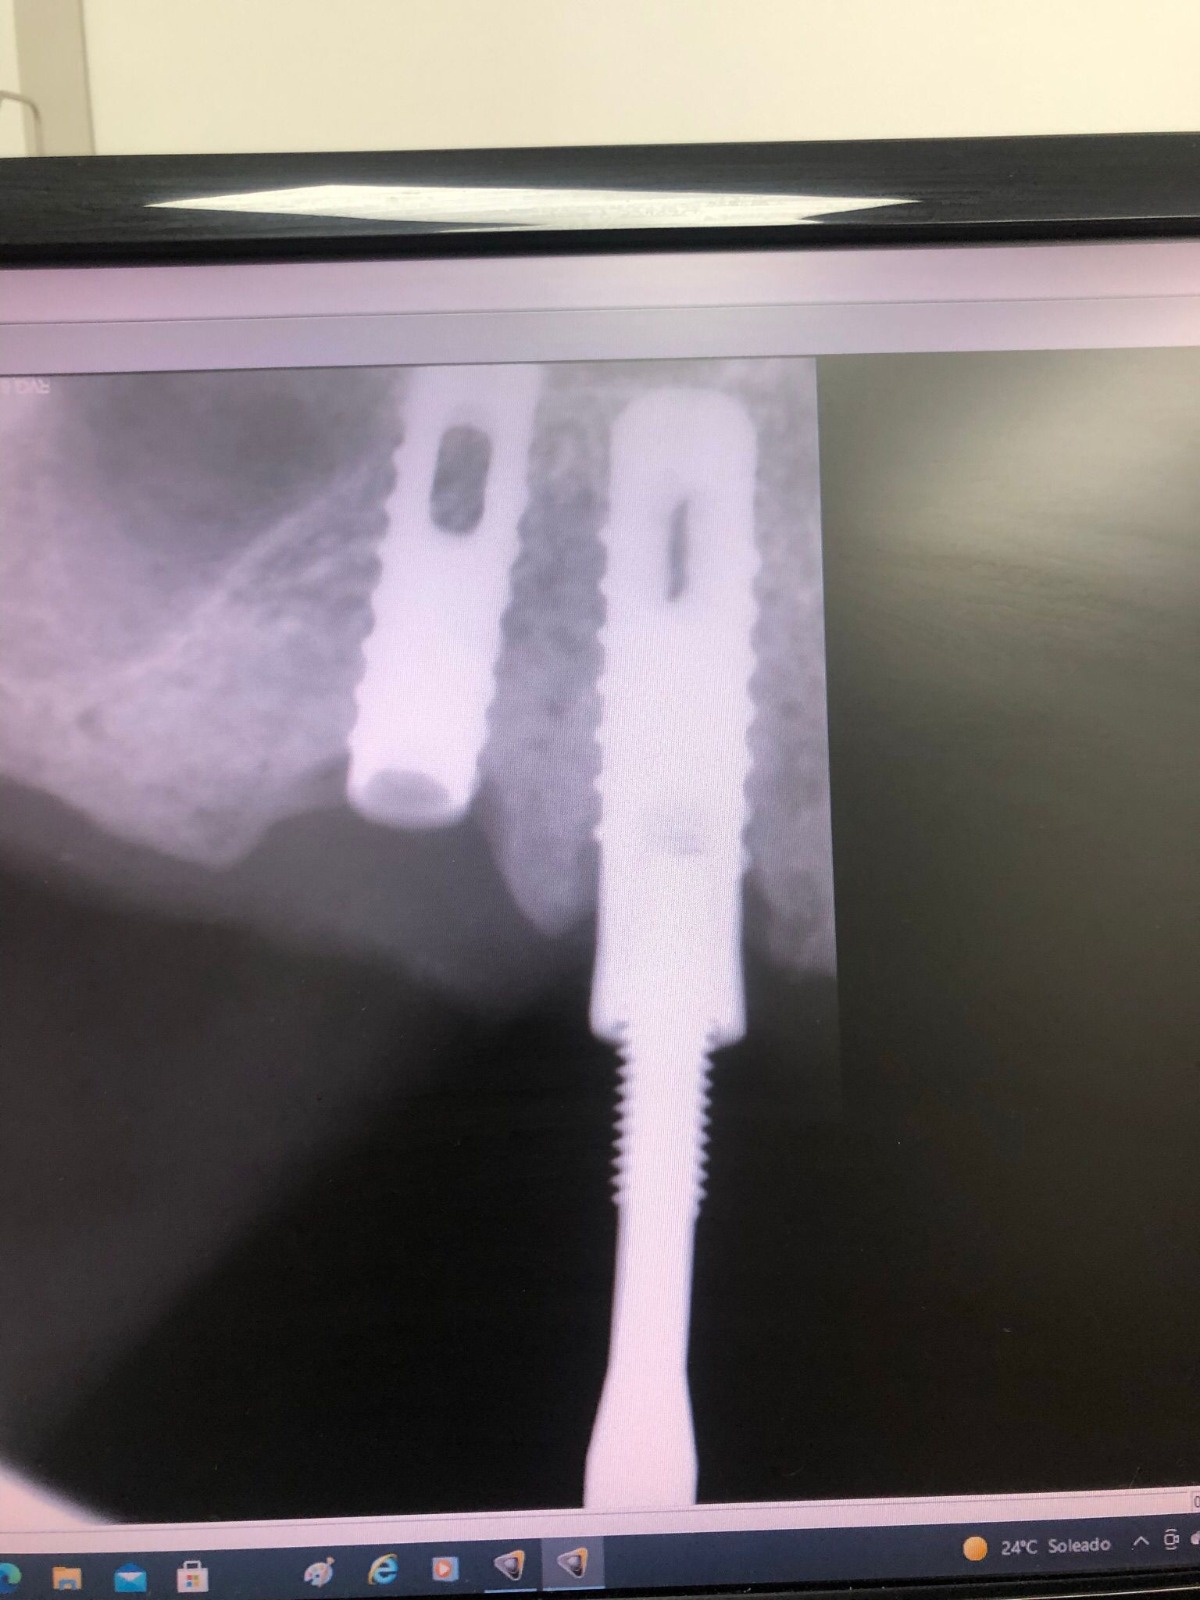

Actualmente vuelve el paciente de nuevo con la misma prótesis. Había roto dos de los tres pilares en concreto los más distales. El primero de los dos había roto la rosca del aditamento dentro del implante como ocurre habitualmente. Pero el ultimo pilar había roto directamente la cabeza del implante tal como se ve en la radiografía y lo que quedaba era un cilindro de titanio macizo perfectamente integrado en el maxilar, sin posibilidad de enroscar nada. Le explicamos al paciente que habría que quitar y poner un implante en el mismo acto. El paciente dijo que no, así que decimos que no se haría cirugía. Buscamos solución alternativa: hacemos un un agujero en el centro del macizo cilíndrico del implante roto y pasamos sucesivamente el set de machos roscantes. Utilizamos una fresa cañón de 1 mm que poco a poco se va introduciendo hasta 8mm con un poco de vagación, que hace que sea un poco mas de 1mm de diámetro. Posteriormente pasamos el conjunto de machos roscantes de métrica 2mm para poder usar un aditamento experimental, que era un palo de rosca de diámetro 2 mm unido a un cuerpo metálico en forma de sombrero napoleónico fabricado en cromo/cobalto, prototipos primitivos de la sistemática ASATIM y que tienen la característica de tener gran resistencia a la fractura. Nos llevó un tiempo largo el tallado de dichos aditamentos, tal como se puede observar en las imágenes, y tras cicatrizar la encía se le hizo una prótesis estándar. Esperemos que no lo rompa más veces.